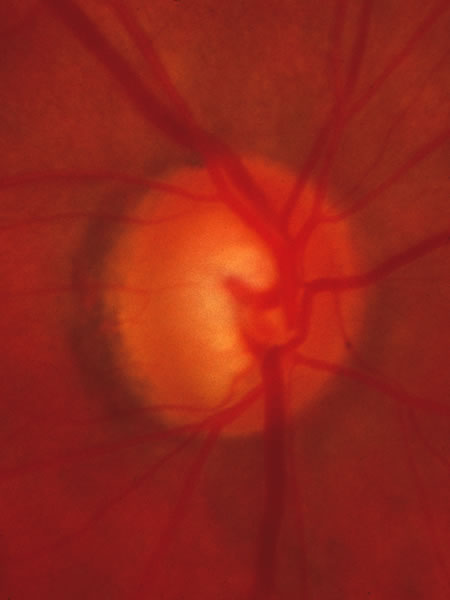

Fig. 37. Swollen optic nerve superiorly during anterior ischemic optic neuropathy caused by giant cell arteritis.

Fig. 38. Same eye after resolution of the attack, with excavation extending to the superior rim of the disc, mimicking the appearance of glaucomatous cupping.

Usually all other forms of optic nerve disease (and inner retinal disease) produce simple atropy of the disc without cupping (Figs. 34 to 36), but occasional cases of cupping have been seen with anterior ischemic optic neuropathy, particularly due to giant cell arteritis (Figs. 37 and 38).